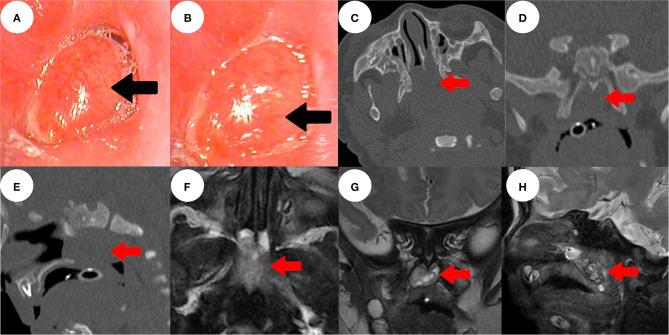

A Rare Case of a Congenital Nasopharyngeal Ganglioglioma With Dyspnea in a 1-Month-Old Male Infant: A Case Report.

A ganglioglioma (GG), a tumor with both neuronal and astrocytic components, rarely occurs outside the central nervous system. We present the first reported case of a 1-month-old male with a congenital nasopharyngeal GG, nasal congestion, and dyspnea; we include the operative video. Magnetic resonance imaging was used to explore whether the tumor communicated with the intracranial space. We used an endoscopic plasma technique to ensure complete tumor resection. This afforded a good visual field, endoscopic magnification, and good hemostasis. We report a rare case of a nasopharyngeal GG triggering nasal congestion and dyspnea in a 1-month-old male, and report our experience with the treatment of nasopharyngeal GG and similar diseases.